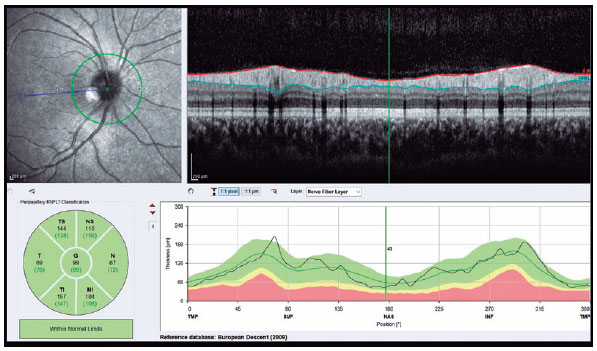

SD-OCT (Spectralis; Heidelberg Engineering, Heidelberg, Germany) was used to visualize the RNFL and choroid. The scan quality ranged from 0 (no signal) to 40 (excellent), and only high-quality images (images with a centered and well-focused optic disc with a signal strength of >20 Db) were selected. The EDI mode was used to improve choroid visualization. Choroidal measurements were performed by two independent experienced physicians who were blinded to the patients. Examinations were performed between 9:00 and 11:00 AM to avoid diurnal variations(11). The right eye values were used for statistical analyses. RNFL thickness was determined using an optic nerve head scan. A volumetric scanning protocol was used to visualize a 15 × 15 region surrounding the optic nerve head (circle scan size: 3.4 mm). The average thicknesses of RNFL and four quadrants (superior, nasal, inferior, and temporal; 90° each) were automatically measured using SD-OCT in the peripapillary area (Figure 1). Choroidal thickness was defined as the distance between the outer retinal pigment epithelial line and the hyperreflective line behind the large choroidal vessel layer at the scleral interface. The thickness was measured manually at 17 different points: at the foveal center and 0.5, 1, 1.5, and 3 mm from the foveal center within the nasal, temporal, inferior, and superior quadrants (Figure 2). Box plots of the OCT measurements for the AN and control groups are shown in figure 3.

The study included 30 patients with AN (26 females and 4 males) and 30 healthy adolescents (23 females and 7 males). The average disease duration in the AN Group was 11.1 ± 9.2 months. The mean age in the AN and Control groups was 15.0 ± 1.6 years and 15.3 ± 1.6 years, respectively. The mean BMI in the Control Group was 22.8 ± 1.6. The demographic and disease characteristics of the participants are summarized in table 1. A comparison of the right eye measurements between the two groups is presented in table 2. The temporal (77.8 ± 11.4 μm vs. 87.5 ± 13.7 μm ) and inferior (132.6 ± 16.1 μm vs. 149.4 ± 15.3 μm) RNFL thicknesses were significantly lesser in the AN Group than in the Control Group (p<0.05). The choroidal thickness in all temporal and inferior regions (0.5, 1.0, 1.5, and 3.0 mm from the fovea) was significantly lesser in the AN Group than in the Control Group (p<0.05). The choroidal thicknesses in the nasal regions 1.0, 1.5, and 3.0 mm from the fovea were also statistically lesser in the AN Group than in the Control Group (p<0.05). In the superior region, the choroidal thickness 0.5 mm from the fovea was significantly lesser in the AN Group than in the Control Group (p<0.05). The central macular (247.6 ± 26.0 μm vs. 266.6 ± 19.5 μm ) and subfoveal (311.8 ± 34.7 μm vs. 337.0 ± 38.2 μm) choroidal thicknesses were significantly lesser in the AN Group than in the Control Group (p<0.05). Our analysis did not reveal a significant correlation between any OCT parameter and the patients' BMI (p>0.05). However, as the disease duration increased, the RNFL thickness in the inferior region significantly decreased (p<0.05). Subgroup analysis revealed no significant difference in any variable between the restrictive and binge-purge AN types. The best-corrected visual acuity was 6/6 in all eyes.